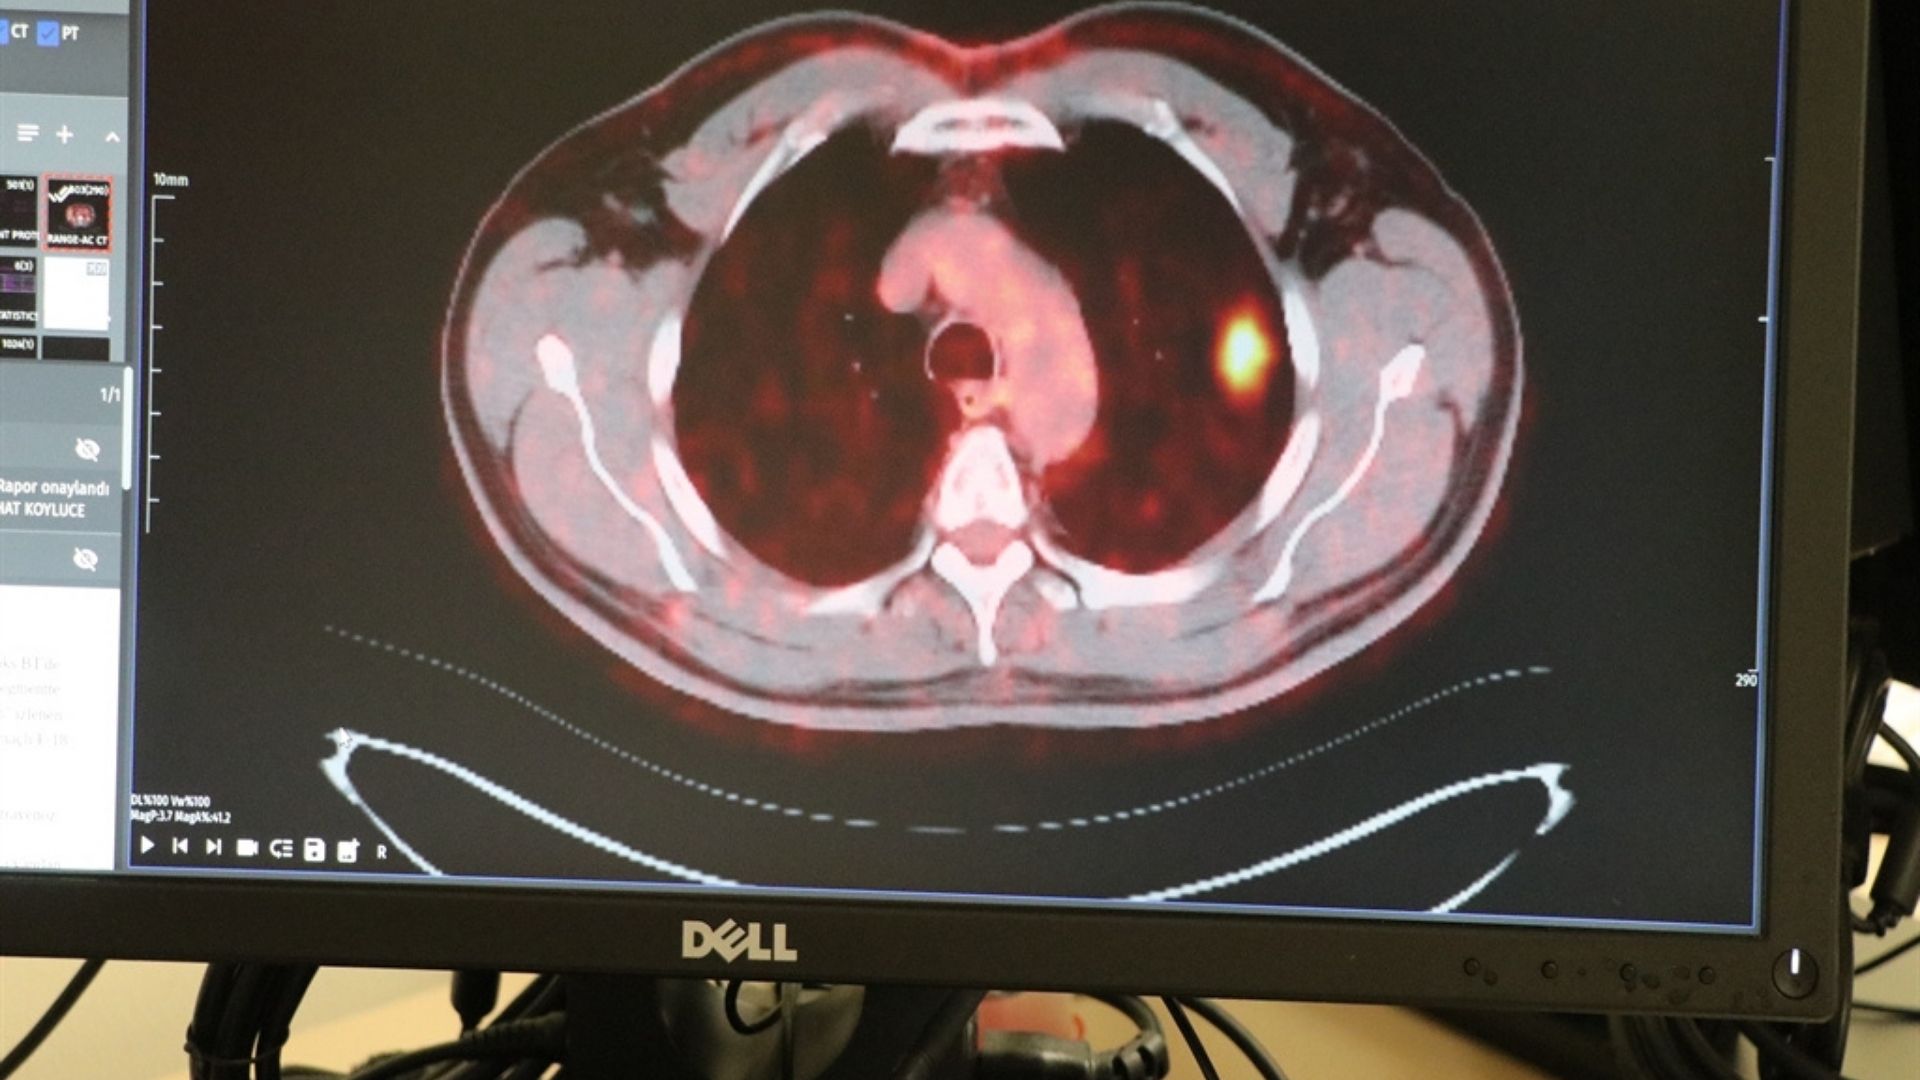

“Tomografide 2 santimlik nodül buldular. Takip edilmesi gerektiğini söylediler. Sonrasında ‘Kansersin Yüksel’ dediler. Şok olmadım, grip olmuşum gibi hissettim. Hayata bağlıyım, yaşamayı seviyorum. Doktorlarıma güvendim ve ameliyat oldum.”

Kayseri Şehir Hastanesi Göğüs Cerrahisi Kliniği’nden Doç. Dr. İbrahim Ethem Özsoy, akciğer kanserinde erken teşhisin kritik olduğunu vurgulayarak şunları söyledi:

“Dünya genelinde yılda 2 milyonun üzerinde kişiye akciğer kanseri tanısı konuyor. Bunların büyük kısmı yaşamını yitiriyor. Türkiye’de yılda yaklaşık 45-50 bin yeni vaka bildiriliyor. Akciğer kanserlerinin yüzde 90’ı sigara içen veya sigarayı bırakmış kişilerde görülüyor.”

Doç. Dr. Özsoy, Ayhan’ın erken evrede tanı aldığı için şanslı olduğunu belirterek şu bilgileri paylaştı:

“Evre 1–2 hastalar cerrahiye uygun oluyor. Ancak 100 hastadan yalnızca 20’si ameliyat edilebilecek durumda bize geliyor. Geri kalan yüzde 80’i geç evrelerde başvuruyor. Hastamız erken yakalandığı için kemoterapi bile almayabilir ve normal yaşamına devam edecek.”